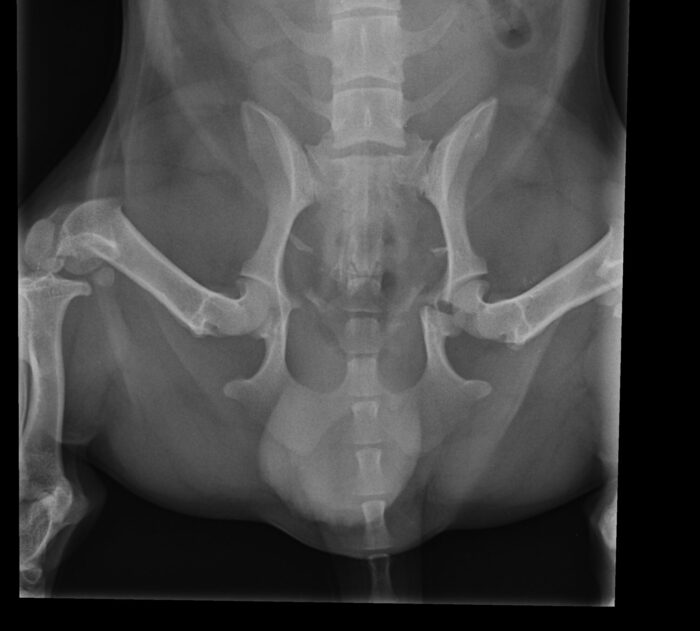

The X-rays revealed the true extent of the injury: a fractured pelvis with a break extending directly through the acetabulum – the socket of the hip joint. It was one of the worst possible configurations of pelvic fracture. Rather than being confined to the flat portions of bone that can sometimes heal with rest, this break ran straight through the joint surface itself.

Fractures involving joints are especially serious. If the joint surface is not restored as close to perfectly as possible, long-term pain, instability and severe arthritis can result. In Dozer’s case, surgery was advised. The goal would be a “perfect” reduction of the fracture to give him the best possible chance of walking comfortably again. However, as with all surgery the procedure was not without significant risks. The sciatic nerve, which runs close to the hip, could potentially be damaged. There was also the possibility that, once visualised directly, the fracture fragments might prove too fragmented or unstable to repair adequately.